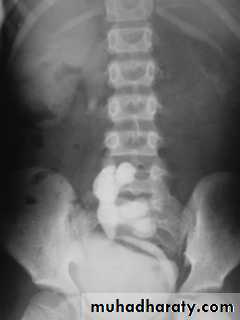

Horse shoe kidney :-*lower poles fused *low positioned kidneys *parallel to spines.*malrotated medially